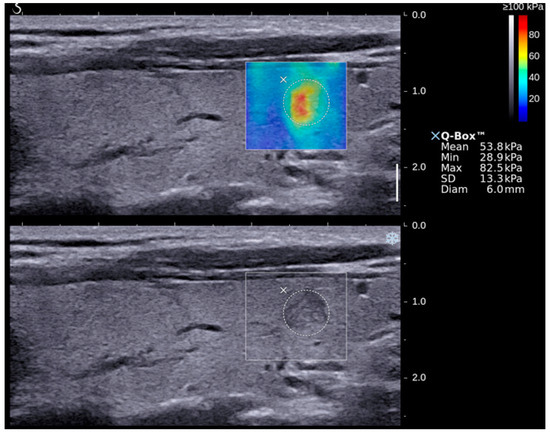

| SWE Indices | Median ± 1 Standard Error | p-Value (95% Confidence Interval) | |

| Benign | Malignant | ||

| Emax | 50.3 ± 3.1 | 85.2 ± 8.1 | <0.05 (50.9–63.5; 73.0–106.1) |

| Emean | 20.2 ± 1.0 | 26.6 ± 2.5 | <0.05 (19.5–23.5; 23.5–33.9) |

| Emin | 3.9 ± 0.6 | 3.8 ± 1.2 | >0.05 (4.2–6.4; 3.7–8.8) |

| Emax (67.3 kPa) | 70.4 | 70.2 | 43.2 | 88.1 | 70.3 | 0.785 |

| Emean (23.1 kPa) | 74.1 | 66.7 | 41.7 | 88.9 | 68.5 | 0.710 |

| GSU + Emax (67.3 kPa) | 70.4 | 83.3 | 57.6 | 89.7 | 80.2 | 0.769 |

| GSU + Emean (23.1 kPa) | 74.1 | 79.8 | 54.1 | 90.5 | 78.4 | 0.775 |